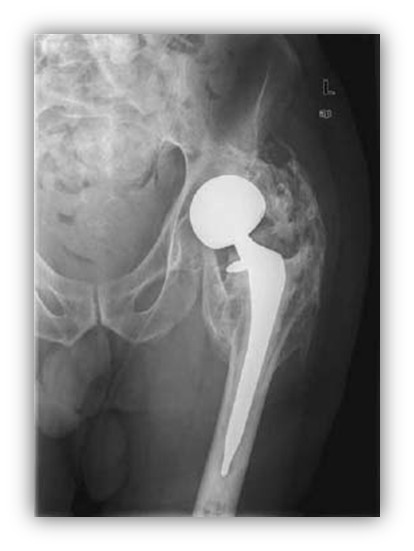

Przed przystąpieniem do operacji wymiany stawu biodrowego z powodu jego zwyrodnienia na tle dysplazji stawu biodrowego należy:

Pytanie 89